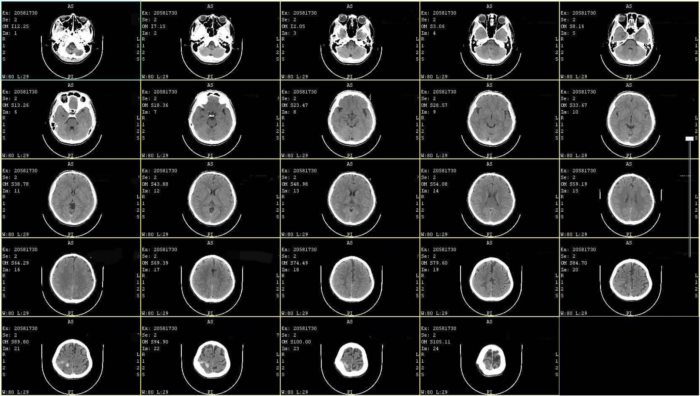

หนุ่มโพสต์ขอความเป็นธรรม ผู้สมัคร ส.ส.พรรคดัง ย่านปทุมธานี ทำร้ายจนกะโหลกยุบ ผ่านมา 17 ปี ไม่เคยเยียวยา คดีไม่คืบ จนกระทั่งหมดอายุความ ต้องก้มหน้ารับชะตากรรม

ตนต้องต้องใช้ชีวิตไปพร้อมกับกะโหลกที่ยุบตัว